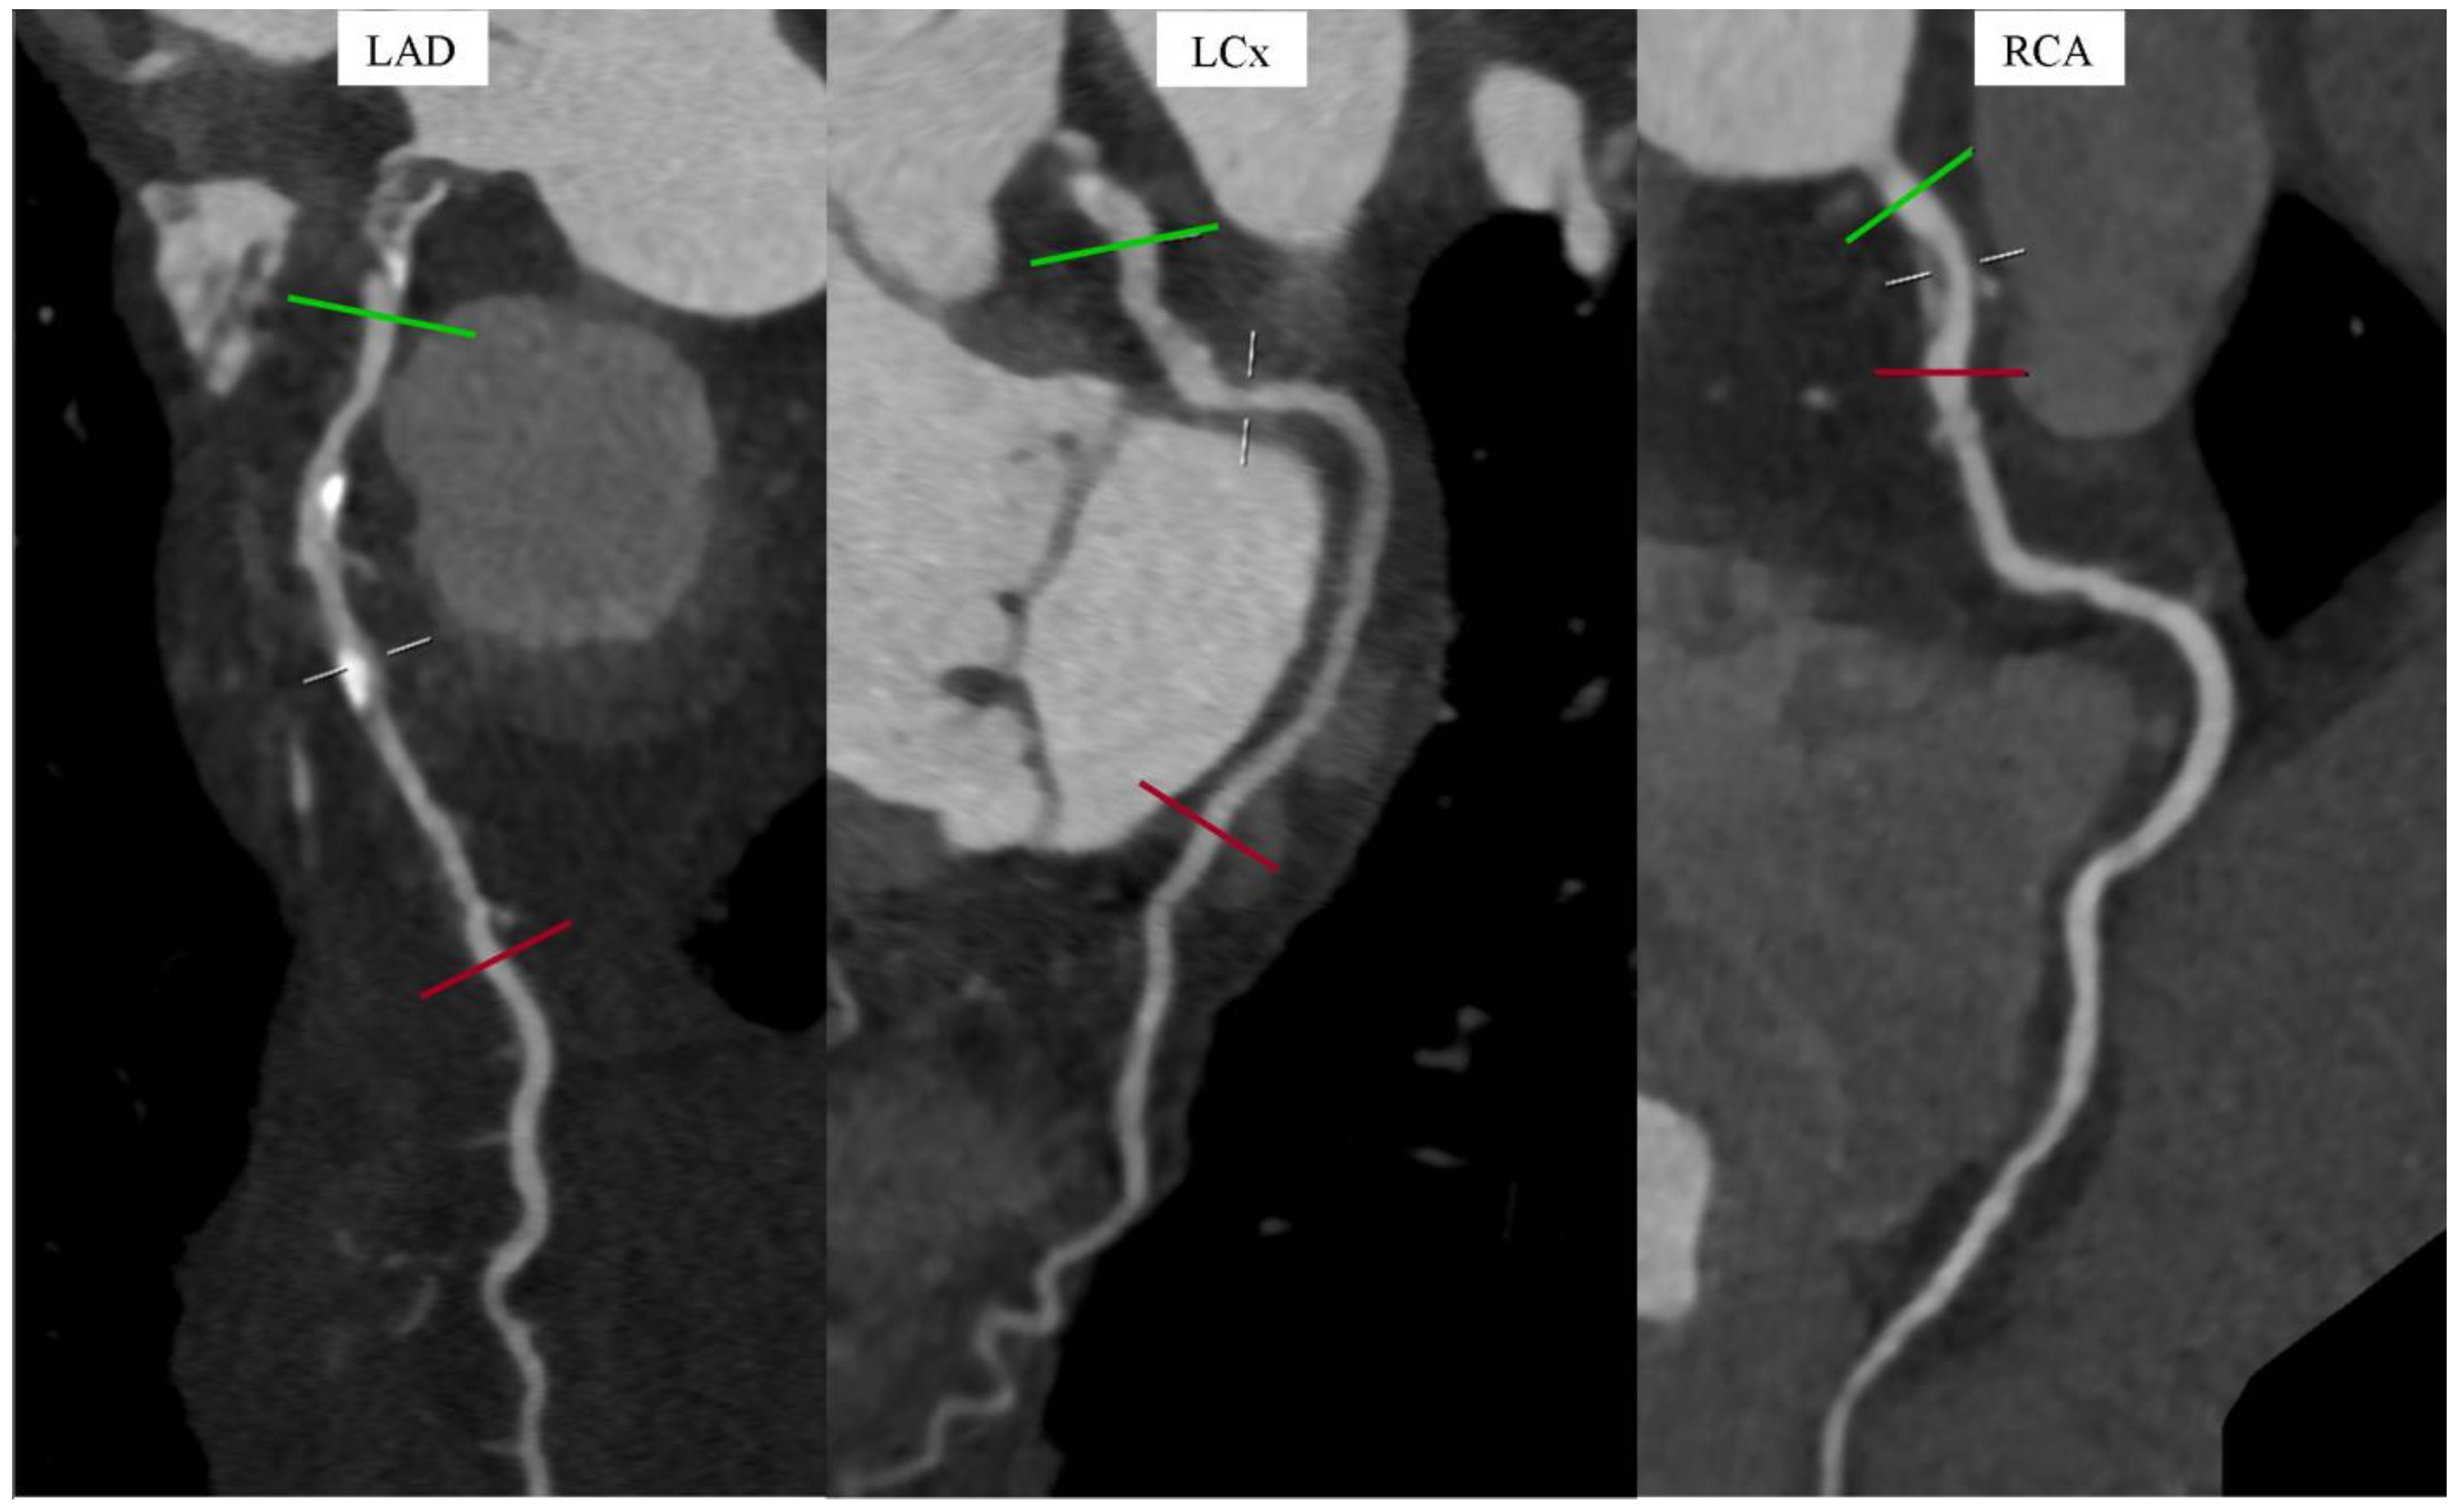

Kugel’s Artery in Coronary Computed Tomography Angiography in a Patient with Left Main Subtotal Stenosis

Gać, P.; Głuszczyk, A.; Plizga, J.; Bińczyk, W.; Dróżdż, O.; Poręba, R. Kugel’s Artery in Coronary Computed Tomography Angiography in a Patient with Left Main Subtotal Stenosis. Diagnostics 2024, 14, 2142. https://doi.org/10.3390/diagnostics14192142